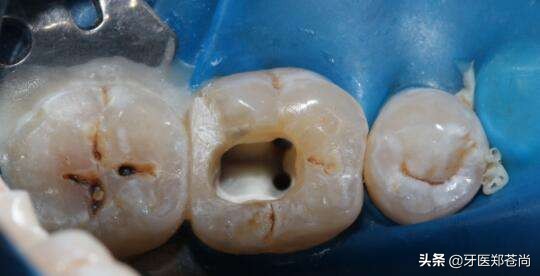

患者提问:我这个根管治疗快做完了,也不疼了,怎么还要做个牙冠呢?(患者有急性牙髓炎)

根管治疗的作用,是治疗牙齿内部病变,制止病变再深入发展,治疗中,患牙疼痛等不适感也会逐渐消失。

修复的是治疗后的患牙牙洞,如果不修复,一方面外面的细菌、脏东西等还会再次进入到牙齿内部,另一方面,治疗后的牙齿比平时的脆弱,如果不修复保护起来,在使用中容易发生崩脆、劈裂。